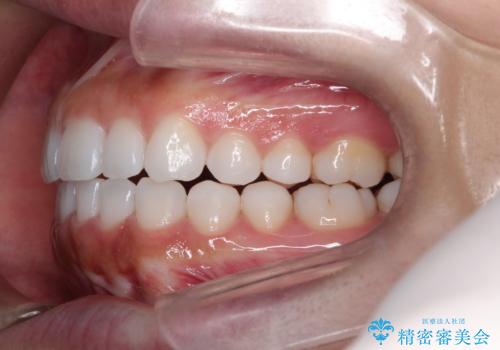

インビザライン治療により、捻転を含む歯列もしっかりと改善しています。

基本的な不正咬合部分は初回の30枚のマウスピースでほぼ改善しており、リファインメントでは前歯部の細かな調整など、患者様の要望を取り入れる形でシミュレーションをセットアップし、満足の行く結果に仕上がりました。